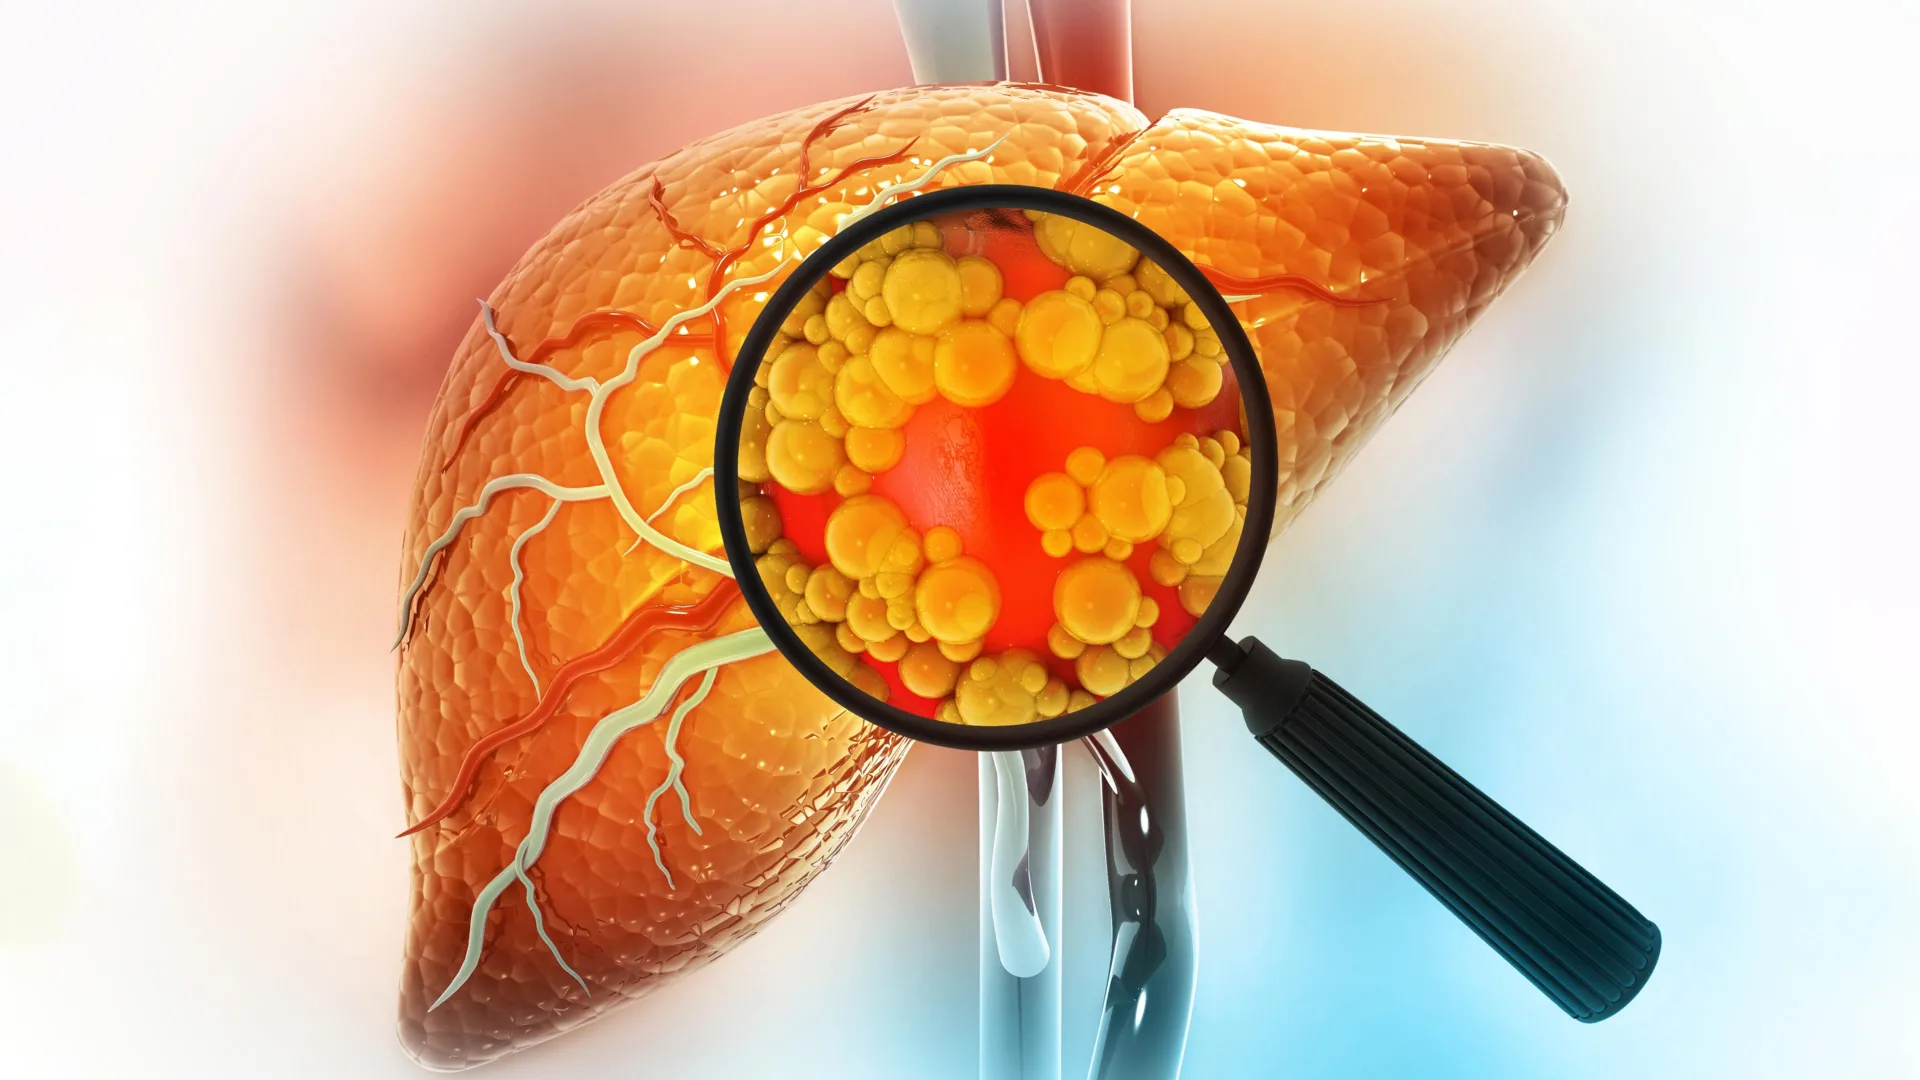

في تطور علمي بارز يقع في تقاطع علوم الشيخوخة والطب التجديدي، نجح باحثون من جامعة كاليفورنيا، لوس أنجلوس (UCLA)، في تحديد مجموعة ضارة من الخلايا المناعية التي تتراكم بصمت في الأنسجة الهرمة ولدى المصابين بمرض الكبد الدهني. هذه الخلايا، التي تُعرف علمياً باسم «الخلايا الهرمة» (Senescent Cells) ويُطلق عليها مجازاً «خلايا الزومبي»، هي خلايا توقفت عن الانقسام نتيجة الإجهاد، لكنها ترفض الموت، وبدلاً من ذلك، تظل نشطة بيولوجياً وتفرز إشارات التهابية مستمرة تسبب دماراً للأنسجة المحيطة بها.

ولم تتوقف الدراسة عند الشيخوخة الطبيعية، بل كشفت أن الكولسترول الضار (LDL) يعد محركاً رئيسياً لهذه العملية. فعند تعريض البلاعم السليمة لمستويات عالية من الكولسترول في المختبر، تحولت إلى حالة الهرم وبدأت في إفراز البروتينات الالتهابية، مما يشير إلى أن الأنظمة الغذائية الغنية بالدهون تسرع من «الشيخوخة البيولوجية» للأعضاء.

الأمر الأكثر إثارة للدهشة هو أن استئصال البلاعم الهرمة لم يبطئ تقدم مرض الكبد الدهني فحسب، بل أدى إلى عكس مساره تماماً؛ حيث استعاد الكبد لونه الأحمر الطبيعي وحجمه الصحي بعد أن كان متضخماً ومصفراً نتيجة ترسب الدهون. كما أظهرت الدراسة أن ذات البصمة الجزيئية (p21 وTREM2) ترتفع بشكل ملحوظ في عينات أكباد البشر المصابين بالمرض، مما يعزز إمكانية تطبيق هذه النتائج على الإنسان.